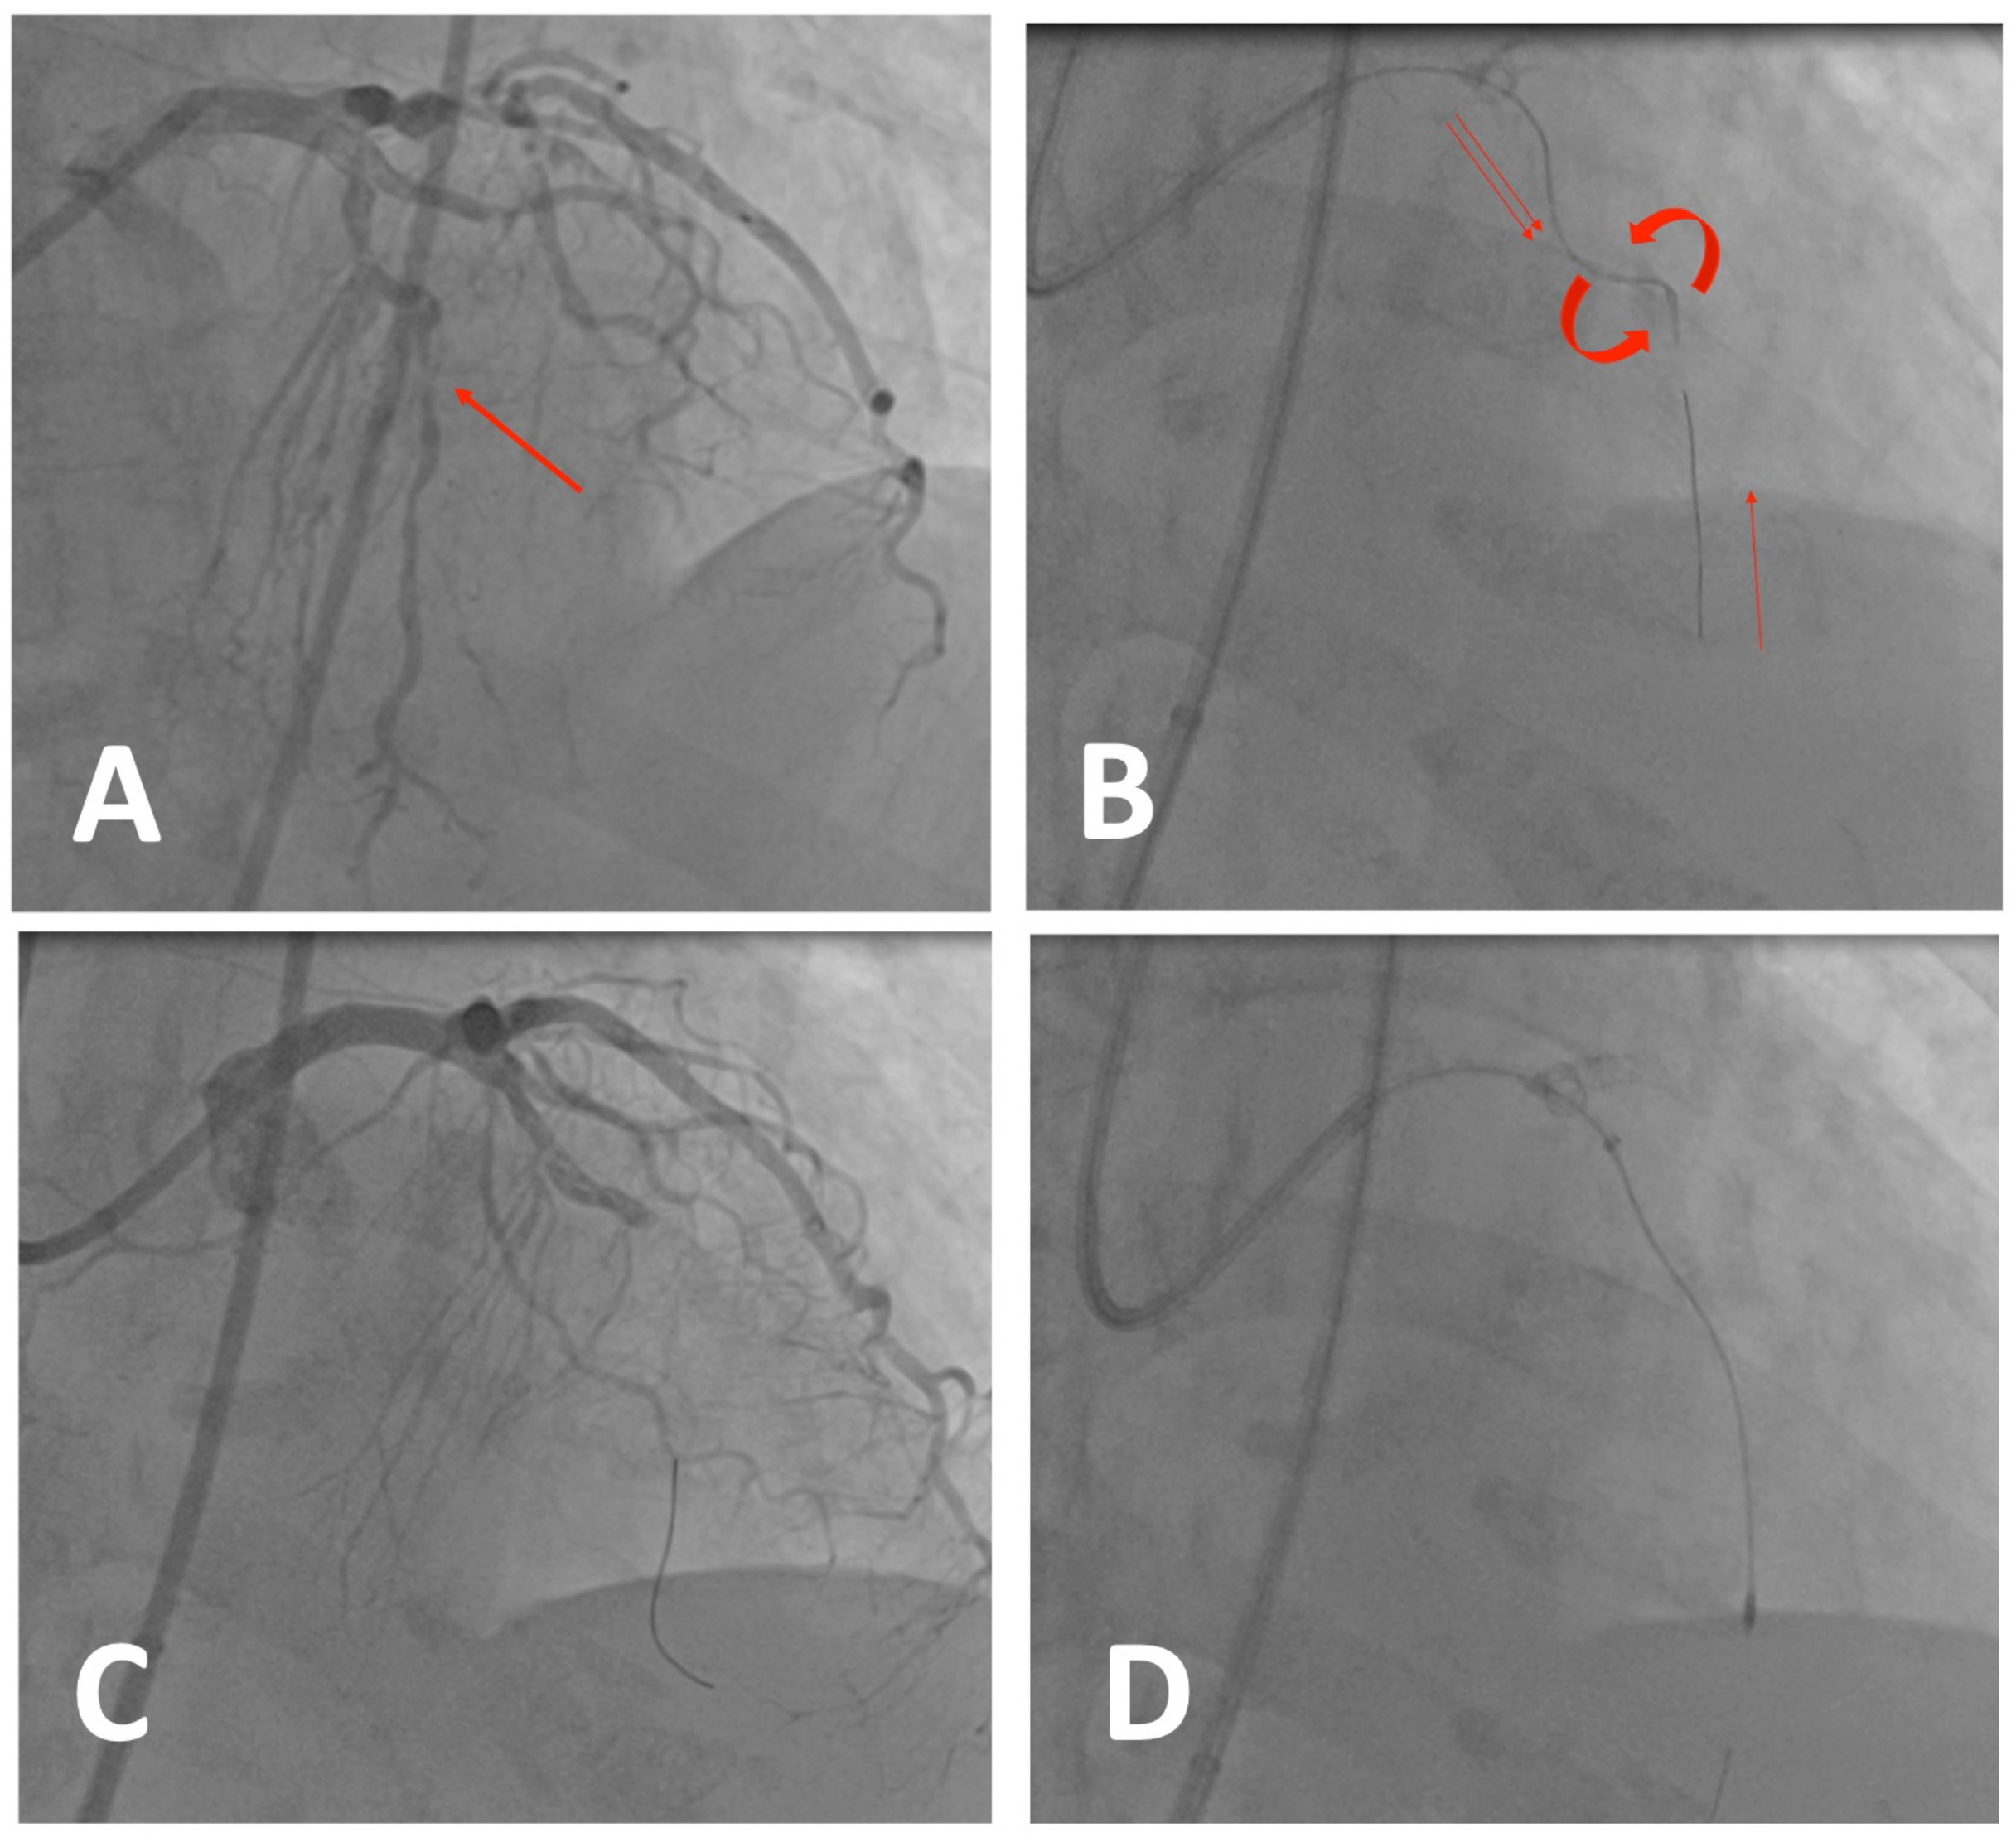

5.3. Case 2